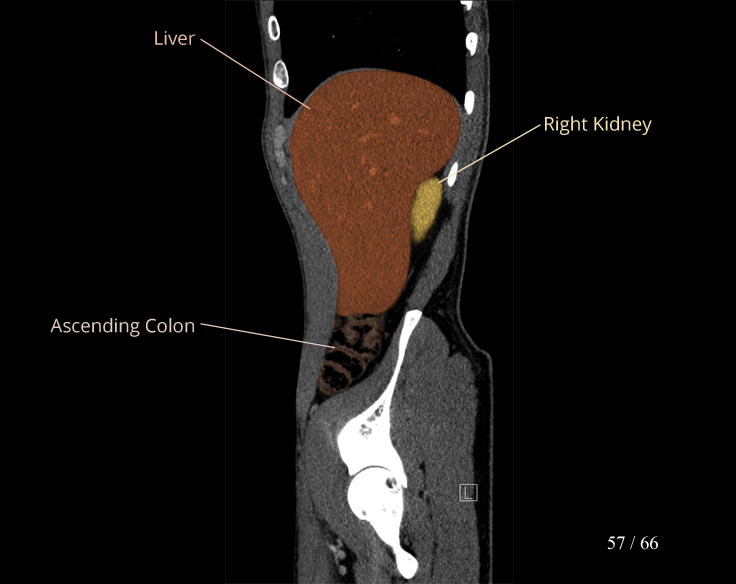

Body

Covers abdominal CT anatomy.